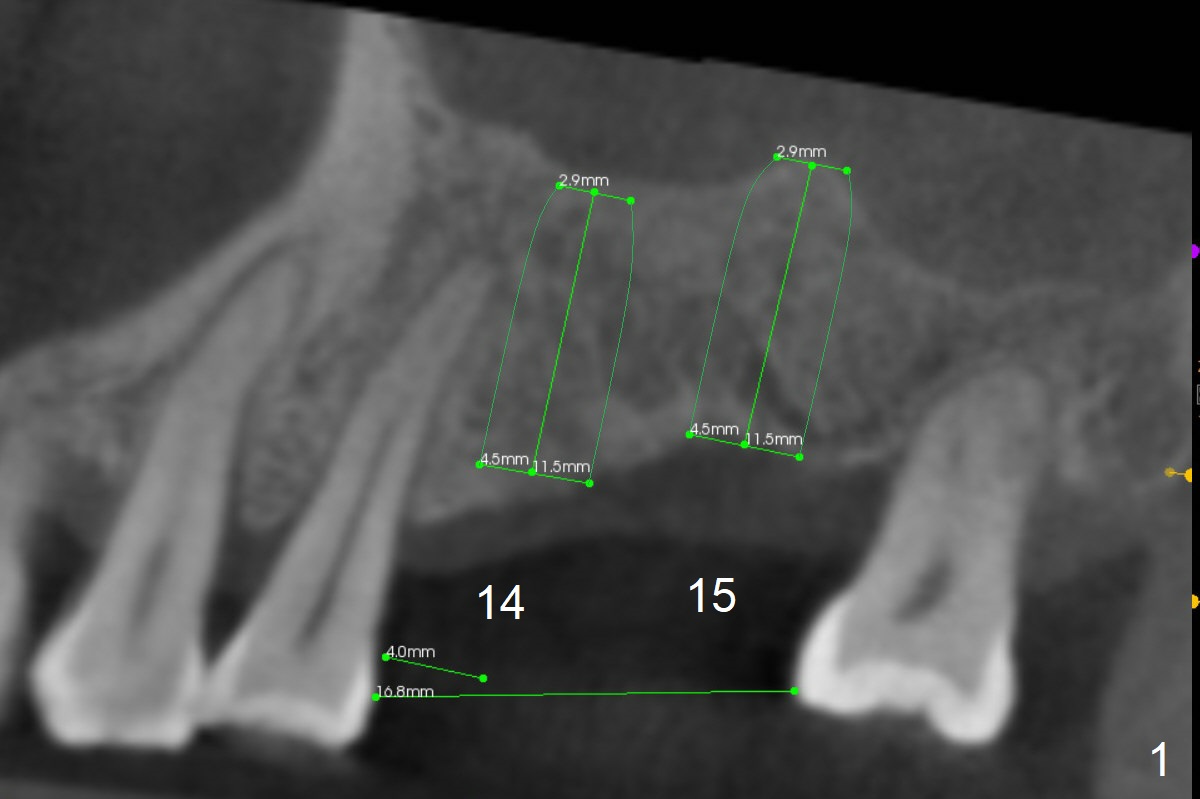

Narrow Mesiodistal Space

A 57-year-old man will return for #14,15 implant placement. The mesiodistal space is narrow (Fig.1: 16.8 mm vs. ~20 mm), whereas the buccopalatal dimension is wide (Fig.2,3 (B: buccal)). The diameters of the 2 implants will be determined by the former parameter. Bone density at the sites are 100-400 units. It is easy for bone expansion/condensation when bone density is 100-200 units.